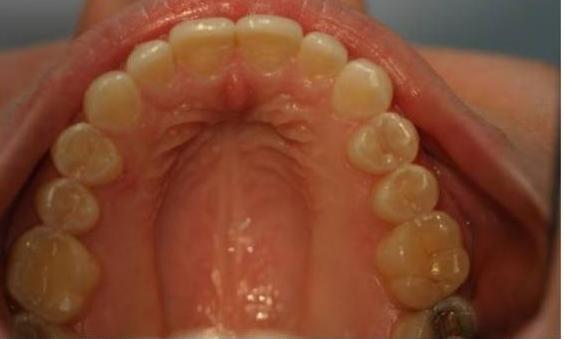

This adult patient had a baby tooth that never fell out, which stuck out like a sore thumb! We started by first removing the baby tooth, leaving the large gap seen in the "before" photo. With Invisalign, we were able to close this gap completely and also fix the mild crowding of their teeth.